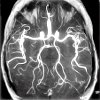

МРТ сосудов головного мозга

МРТ сосудов головного мозга. Диагностический метод для изучения строения сосудов головного мозга и характера кровотока. Этот метод позволяет визуализировать артерии, вены и венозные пазухи, чтобы оценить характеристики кровотока и его кровообращения в тканях мозга. В процессе МР ангиографии могут быть обнаружены компрессия, окклюзия, воспаление или нарушение целостности сосудистой стенки, порок развития, артериовенозный свищ, кровотечение. МРТ головного мозга не требует специальной подготовки. Перед контрастом оценивается функция почек и выявляется история аллергических реакций.

МРТ сосудов головного мозга основана на явлении ядерного магнитного резонанса. Суть его заключается в кратковременном колебании протонов ядер атомов водорода с образованием собственного магнитного поля, которое фиксируется аппаратом. Кровообращение в сосудах может значительно улучшить сигнал МРТ во внешнем магнитном поле. Это называется явлением импульсного потока (эффект). В радиологии существует два типа таких сигналов. Первый - это время полета, которое включает в себя эффект «улучшения потока в потоке» (эффект «притока») и эффект «потери сигнала» (нулевой поток), второй - фазовый контраст. Эти явления играют ключевую роль в исследовании кровеносных сосудов при церебральной ангиографии с помощью МРТ, поскольку они позволяют визуализировать сосудистое русло без дополнительного применения контрастных веществ. Этот метод широко используется в неврологии, нейрохирургии, травматологии и онкологии.